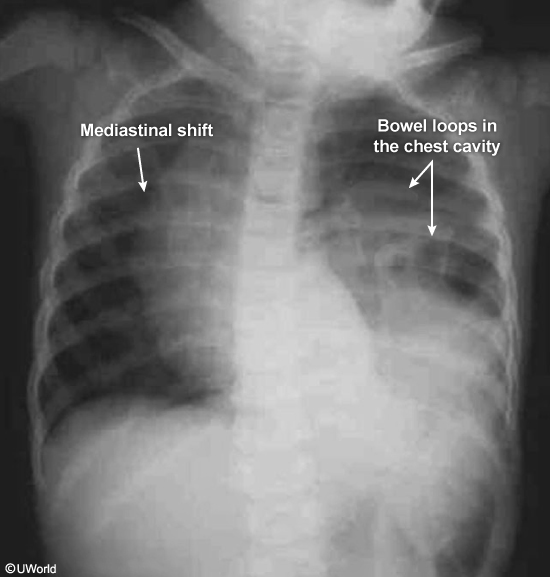

Diaphragmatic ruptures most commonly occur on the left, because the liver prevents right-sided rupture. Two radiographic findings on chest x-ray are multiple air-fluid levels and presence of nasogastric tube in the thorax.

Blunt abdominal trauma due to motor vehicle accident can significantly raise intra-abdominal pressures and lead to diaphragmatic rupture or avulsion from its attachments. The left diaphragm is more prone to injury than the right due to congenital weakness in the diaphragm's left posterolateral region and the liver's protective effects on the right side. Some patients (especially children) with traumatic diaphragmatic injury may initially have no symptoms or signs and can have a delayed presentation (months to years) with expansion of the diaphragmatic defect and herniation of abdominal organs. This delayed diagnosis is associated with a high morbidity and mortality and can increase the risk of hernia formation and strangulation.

Elevation of the hemidiaphragm on the chest x-ray might be the only abnormal finding, but ultrasonography or CT scan of the chest is sometimes required if the chest x-ray does not visualize the area well. The small bowel is sometimes present in the thoracic cavity.

The treatment is surgical correction.